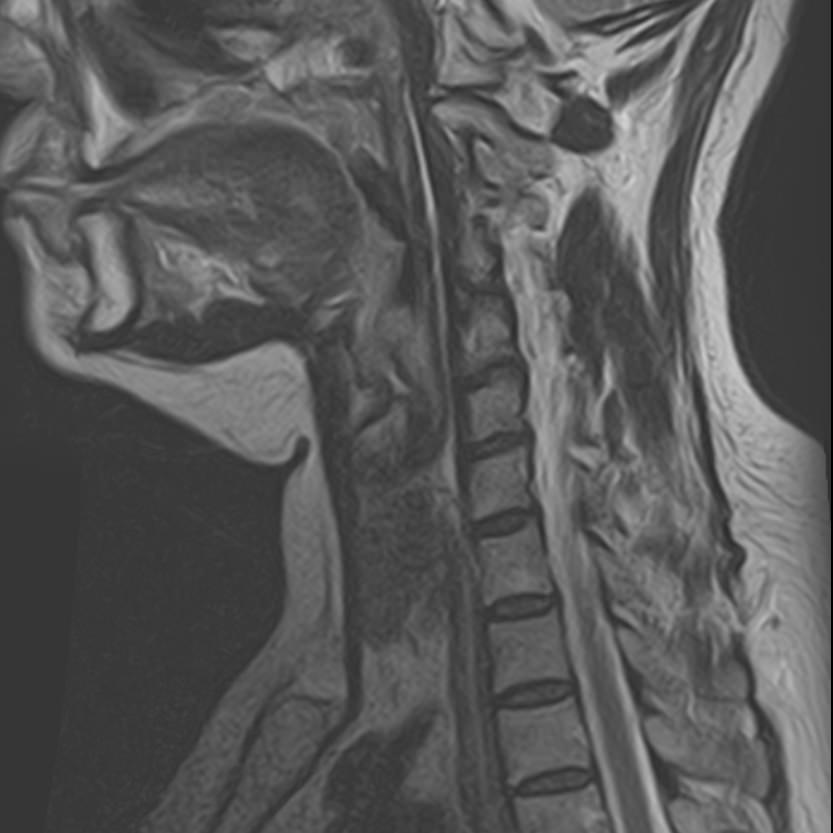

Магнитно-резонансная томография шеи предусматривает детальную визуализацию различных анатомических структур области шеи. Сюда входит полость рта, язык и корень языка, пищевод, гортань, окологлоточные лимфоузлы, шейные лимфоузлы, слюнные железы, щитовидная железа, мышцы и межфасциальные пространства.

В нашей клинике данное обследование выполняется на новейшем 32-канальном высокопольном томографе закрытого типа TOSHIBA VANTAGE TITAN 1,5 Тесла. Высокотехнологичный аппарат производит сканирование путем тончайших срезов с шагом от 1 мм в трех различных плоскостях. Используя современные компьютерные программы, полученные данные преобразуются в 3D-изображение исследуемой зоны. Это обеспечивает точность и достоверность диагностики заболеваний анатомических структур, расположенных в области шеи.